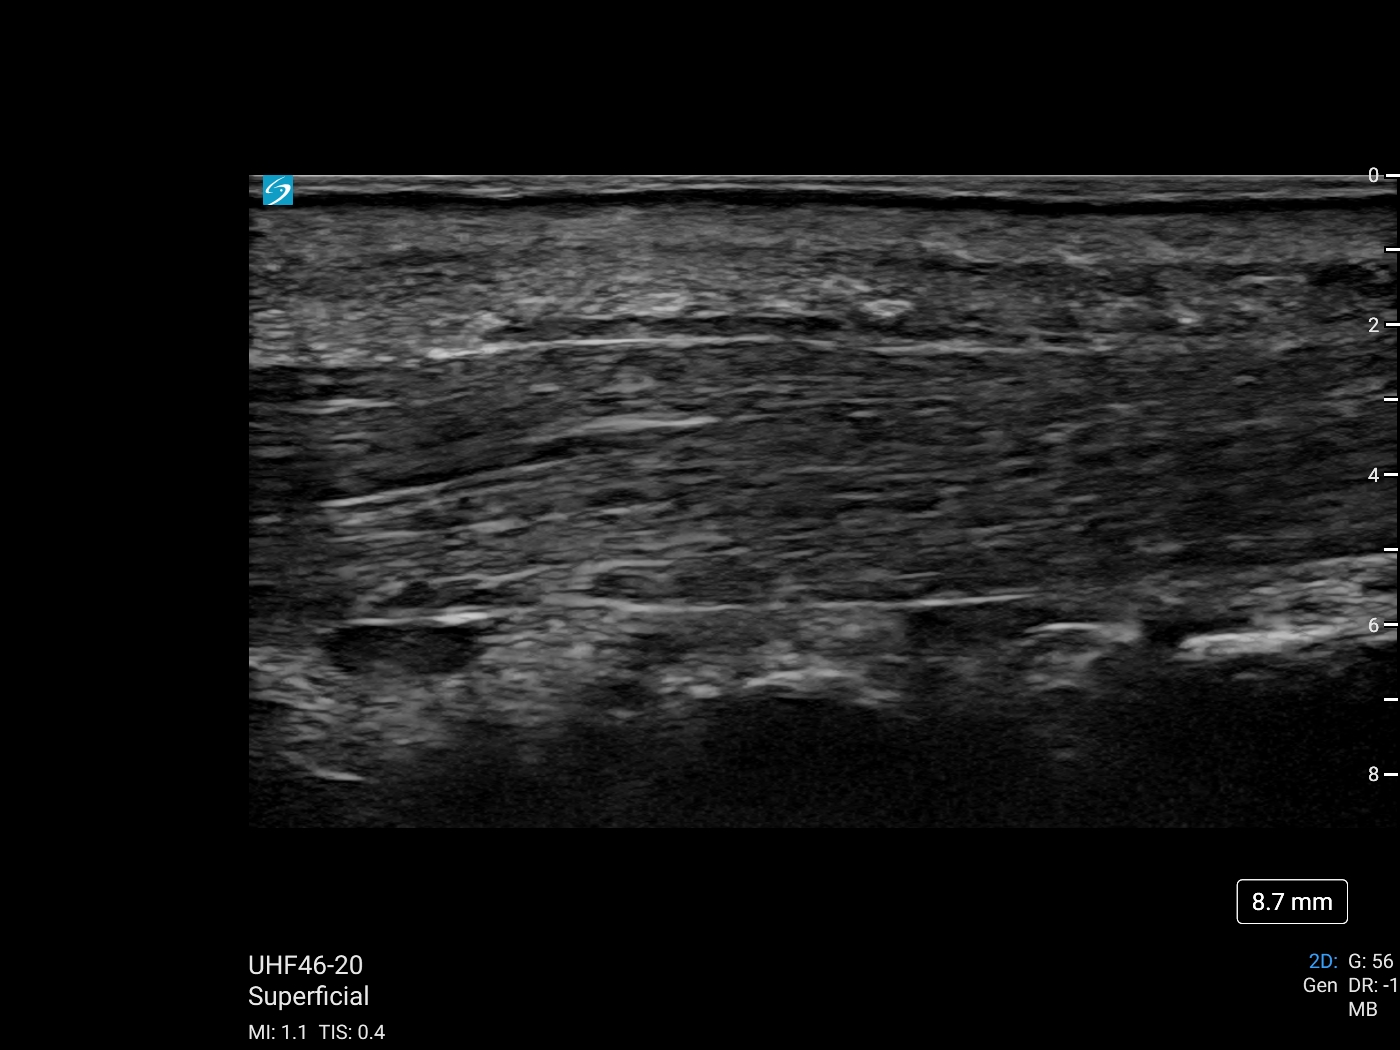

Ultrasound enables the detailed assessment of soft tissue, connective tissue, nerves, and vascular structures of the volar hand, now enhanced with Sonosite’s new ultra-high frequency transducer: UHF 46-20 MHz. Join Daniel Shelton for Part 2 of the Diagnostic Hand Ultrasound Series: ‘Introduction to the Volar Hand’ to review superficial anatomy of the volar hand, the advantages of ultra-high frequency for detailed volar hand imaging, and techniques that help enhance image clarity and distinguish tissue layers.

Thumb Flexor Tendon with UHF